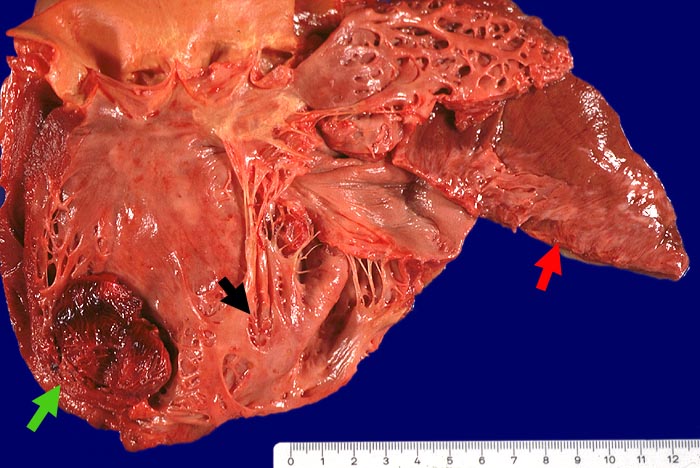

Thrombosiertes Herzwandaneurysma, Myokardinfarktnarbe

Myokardinfarktnarbe der Hinterwand, der Vorderwand und des Septums (14x8cm). Thrombosiertes Herzwandaneurysma des Septums (4x8cm)im Bereich der Narbe. Abrundung der Herzspitze und Vergrösserung des Herzens (exzentrische Hypertrophie).

Schwere stenosierende Sklerose des Ramus interventricularis anterior der linken Koronararterie.

St.n. Myokardinfarkt vor 3 und 10 Jahren. Low-Output-Syndrom.